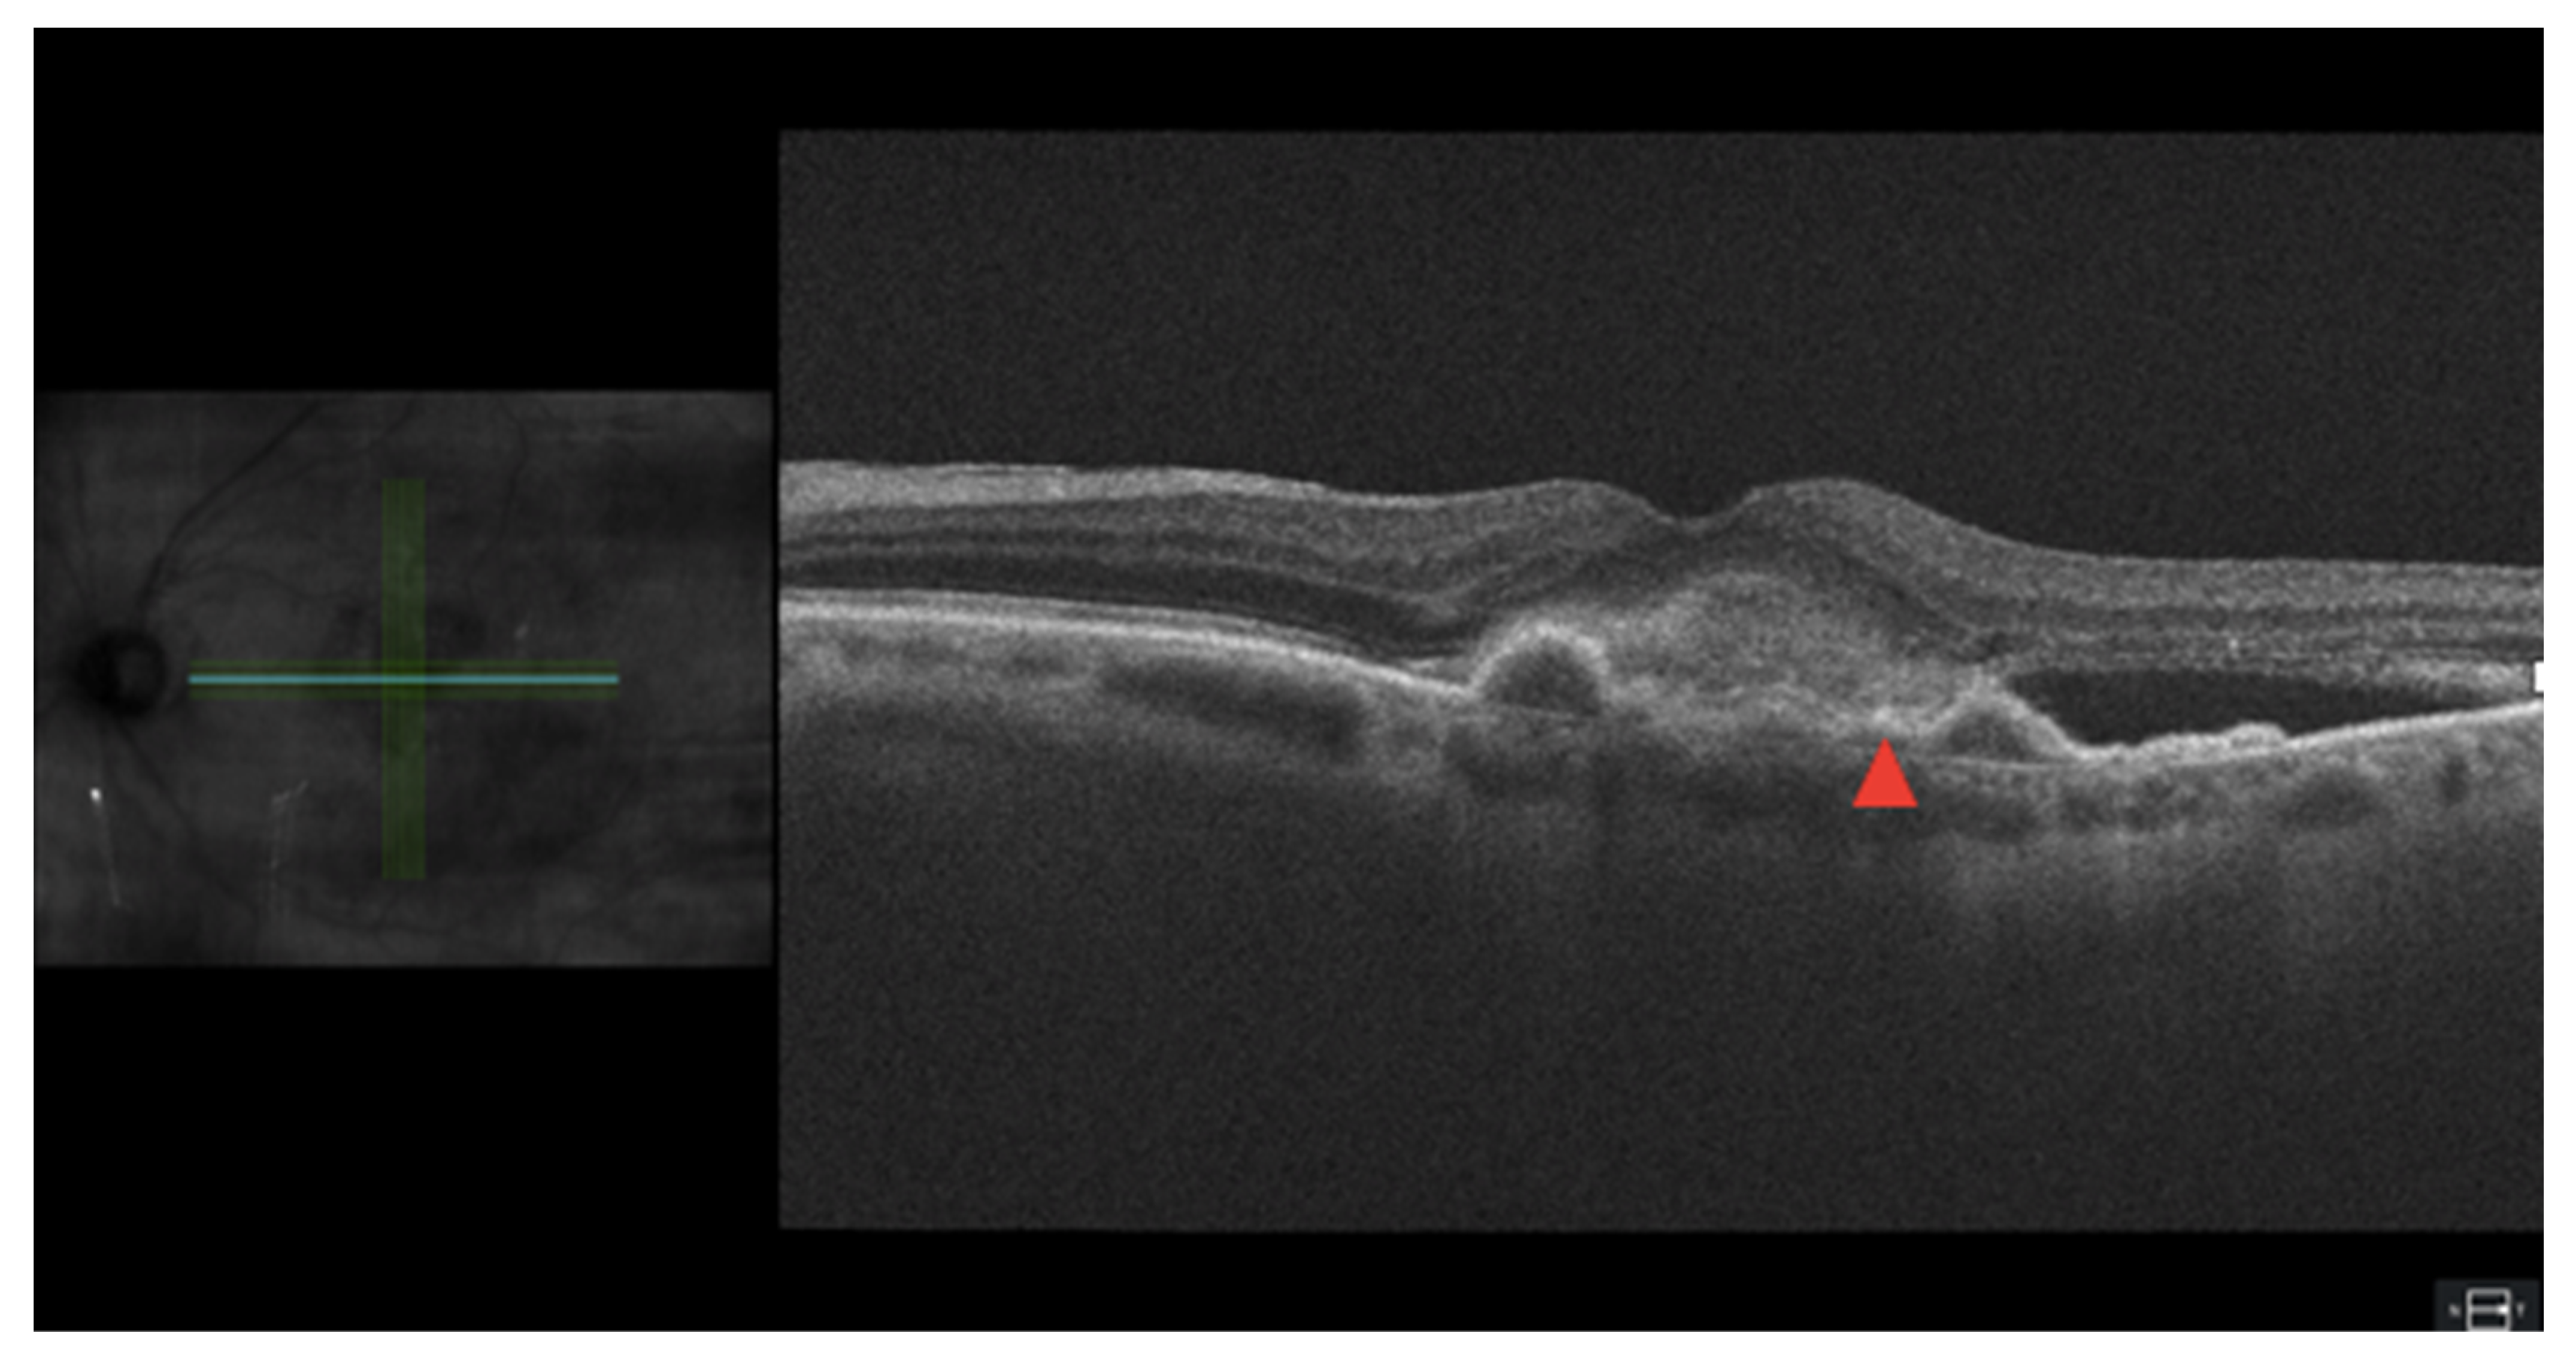

3.6. Pigment Epithelial Detatchment

- Cheong, K.X.; Teo, K.Y.C.; Cheung, C.M.G. Influence of pigment epithelial detachment on visual acuity in neovascular age-related macular degeneration. Surv. Ophthalmol. 2020, 66, 68–97. [Google Scholar] [CrossRef]

- Mrejen, S.; Sarraf, D.; Mukkamala, S.K.; Freund, K.B. Multimodal Imaging of Pigment Epithelial Detachment: A Guide to Evaluation. Retina 2013, 33, 1735–1762. [Google Scholar] [CrossRef]

- Hoerster, R.; Muether, P.S.; Sitnilska, V.; Kirchhof, B.; Fauser, S. Fibrovascular Pigment Epithelial Detachment is a Risk Factor for Long-Term Visual Decay in Neovascular Age-Related Macular Degeneretion. Retina 2014, 34, 1767–1773. [Google Scholar] [CrossRef]